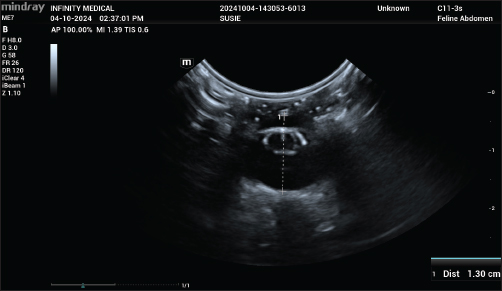

Ocular dimensions were assessed using B-mode ultrasonography with an 3-11 MHz micro convex probe (ME 7, Mindray, Shenzhen, China; and, MyLab Alpha; Esaote, Genoa, Italy). Coupling gel was applied to the probe, which was then gently placed between the retracted eyelids and onto the cornea at the same time under minimal pressure to avoid distortion of ocular measurements (Fig. 1C). The default sound wave velocity of the ultrasound system for ocular tissues was set at 1540 m/s.

Preoperative measurements, including preoperative ACD, crystalline lens thickness (CLT), and AGL, were obtained using the internal calipers of the ultrasound system in the captured images (Fig. 2). The measurements were performed by an ophthalmologist. Each parameter was measured once for each image in three separate images, and the average of the three readings was recorded (Table 1).

Fig. 2. Axial globe length (AGL) measured using internal calipers on B-mode ultrasonograhy.